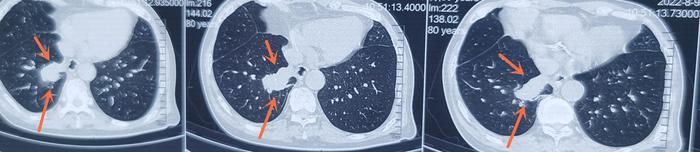

今天门诊见到一例80岁肺癌患者,已经晚期发生多发骨转移了。全身疼痛1月。患者女儿说4年前患者仅仅有10毫米的一个磨玻璃结节

这个磨玻璃结节现在的终点是一个50×25毫米的右下肺癌,4年前的起点是一个10毫米的磨玻璃结节。

目前肿瘤大小为50×25毫米的右下肺癌,大约15个骨转移灶,根据我的推测,大约18个月前还没有骨转移灶,这时肺癌的大小为23×9毫米,这时还有手术机会。